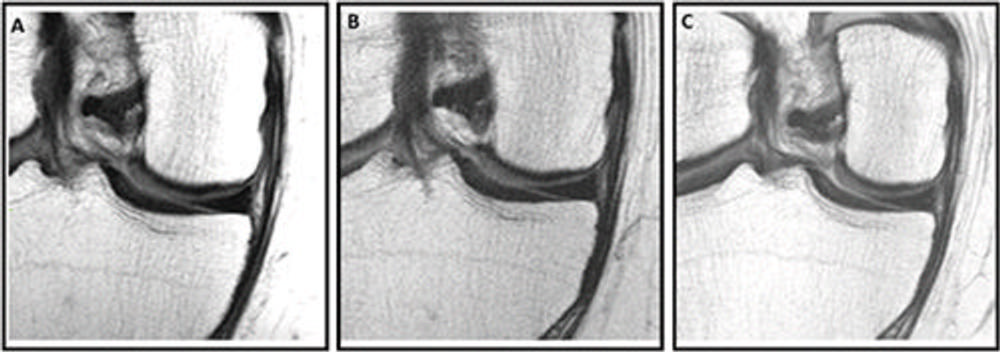

Figure 2. Knee MRI scans in a 58-year-old female participant in the Osteoarthritis Initiative who was administered a corticosteroid injection. Sagittal intermediate-weighted images obtained (A) 2 years before injection, (B) at the time of injection, and (C) 2 years after injection show a focus on the medial femoral cartilage and trochlea. (C) The postinjection scan shows a new full-thickness cartilage lesion in the medial femoral cartilage (arrowhead), whereas images from the preinjection time points show a well-preserved medial femoral cartilage (A, B) . The postinjection scan (C) also shows the development of a new full-thickness cartilage lesion in the medial femoral cartilage and a new bone marrow lesion in the trochlea (arrow), both of which were absent in the preinjection scans. These findings suggest structural deterioration following the corticosteroid injection.